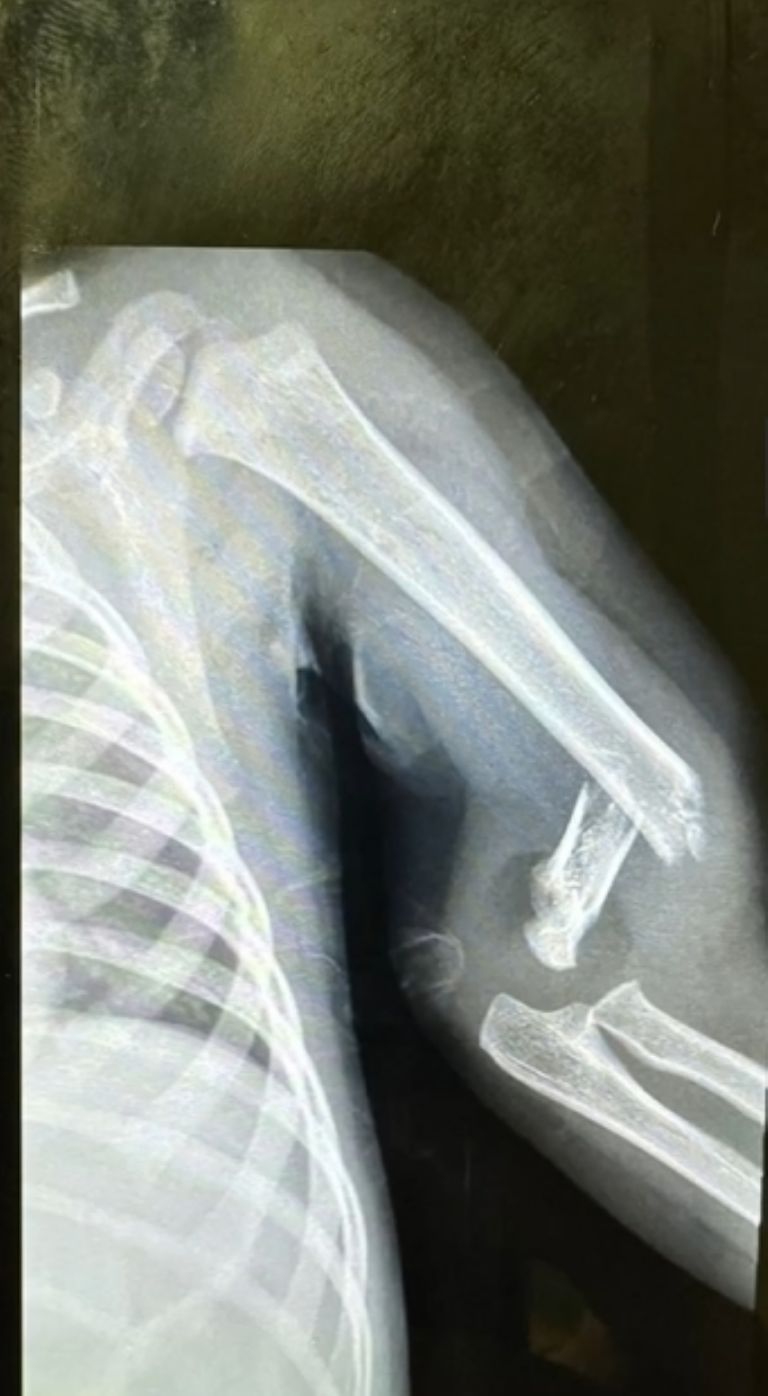

Créditos: Instagram @musamistral

De manera consecutiva, Marcela Mistral estuvo compartiendo algunos videos sobre el proceso de recuperación de Toñito De Nigris, en los que ella lucía demacrada y alerta para evitar que su pequeño sufriera mayores daños. A casi 1 mes de toda esta penosa situación, la rubia compartió un nuevo video en el que mostró cómo fue que tanto ella como Poncho se encargaron de cuidar al infante, mientras que en el pie de página incluyó un texto donde daba una noticia.

Resulta ser que, luego de un largo y duro periodo de recuperación, Toñito se encuentra mucho mejor, puesto ya le retiraron el yeso, aún así, Marcela destacó que se encargará de cuidar a su hijo para que logre recuperar las fuerzas en el brazo que tuvo lesionado: “Bendito Dios hoy le quitaron todo… seguiremos cuidándolo para que se ponga fuerte, fuerte, fuerte”, declaró la celebridad en su cuenta oficial de Instagram.